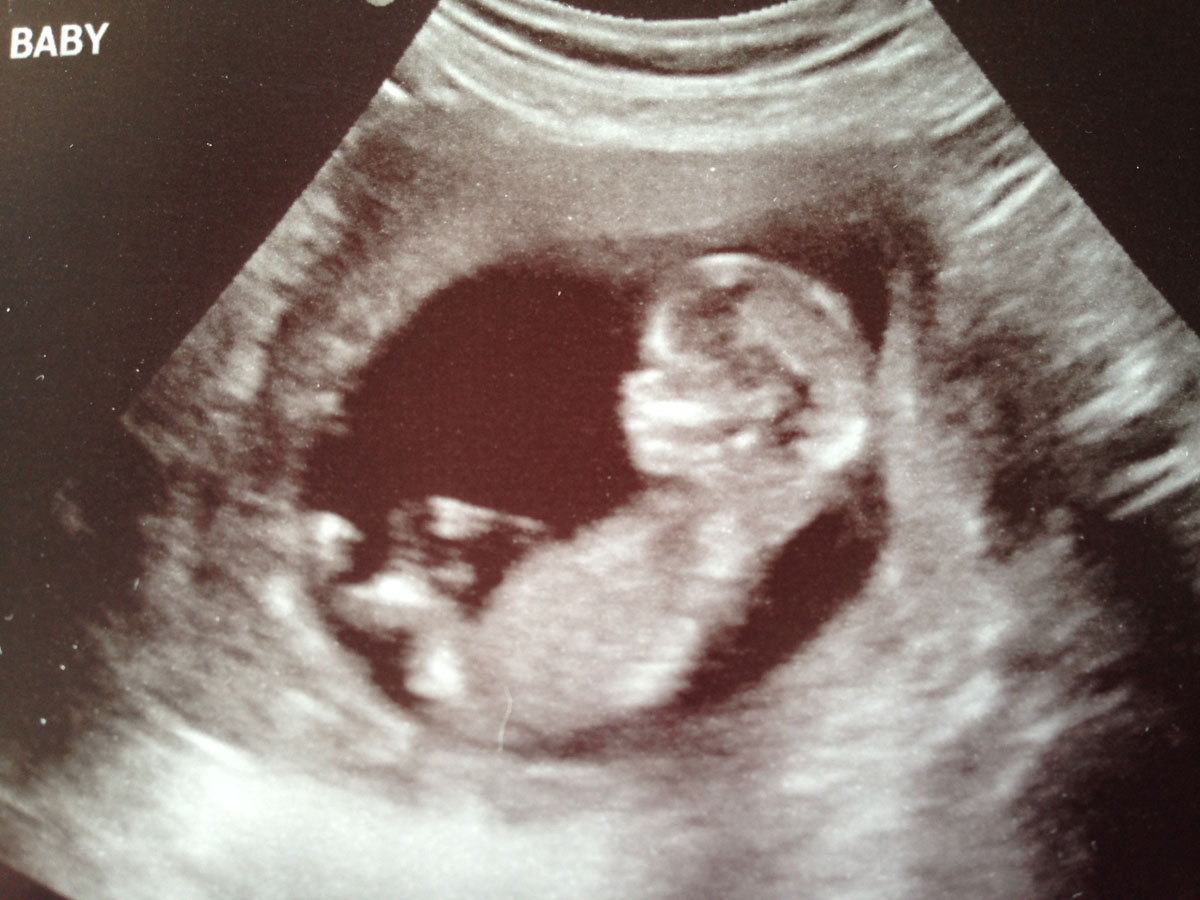

I've been reading up on nubs for weeks and still really have no idea what I'm looking at. I'd reeeally appreciate any guesses on these!

I'm not seeing any clues sorry :)

No nub

no nub sorry legs are in the way!

Skull looks girlish though !